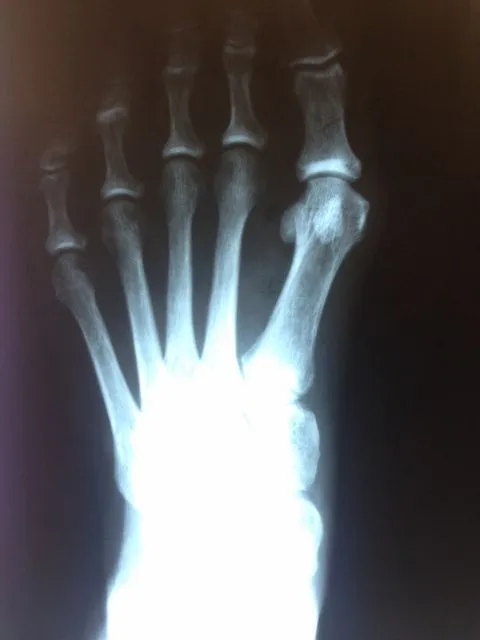

In the x-ray image below is a Hallux Valgus or what is more commonly known as a bunion deformity where the great toe is deviated towards the lesser toes causing abnormal structure which is a result of genetics, abnormal shoegear and abnormal mechanics will cause wearing of the joint and enlargement of the head of the long bone called the first metatarsal.

Post-surgical repair of the same patient bunion deformity with the great toe now in rectus (straight) position with surgically placed screws in the head of the first metatarsal that were used to secure fixation of the cut made across the bone to translate the head of the bone laterally in order to reduce the deformity. The screws will remain in place even after the bone heals.